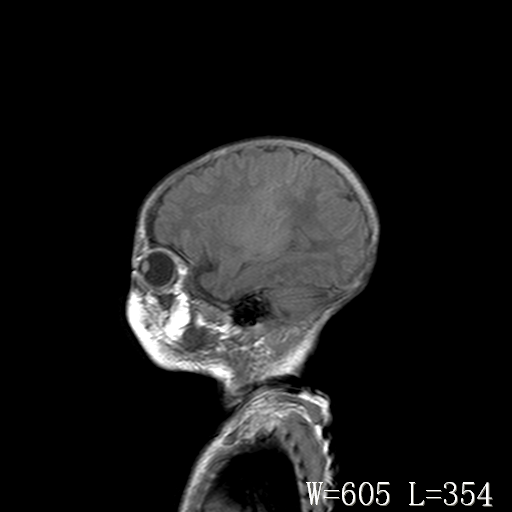

标题: PED3338:脑部病变?

男,4天,发复抽搐1天。

新生儿正常颅脑

脑干形态欠规则,信号增高,不知怎么解释?

脑干背侧面t1高信号是,新生儿正常已经髓鞘化好的部位